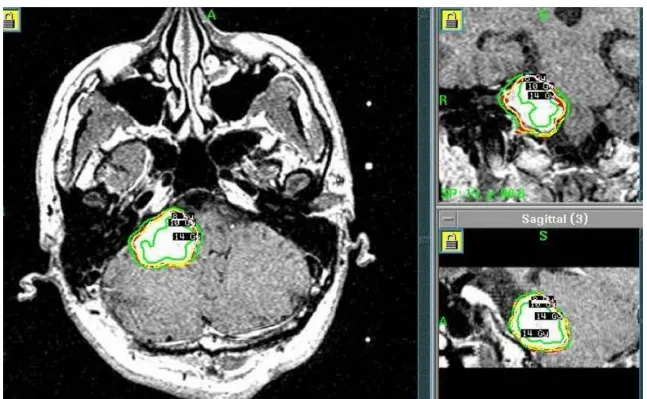

伽玛刀放射外科治疗计划

2005年8月:为控制术后残留肿瘤,他接受了伽玛刀治疗。

B.2005年8月,第一次手术后、伽玛刀治疗前的MR图像。